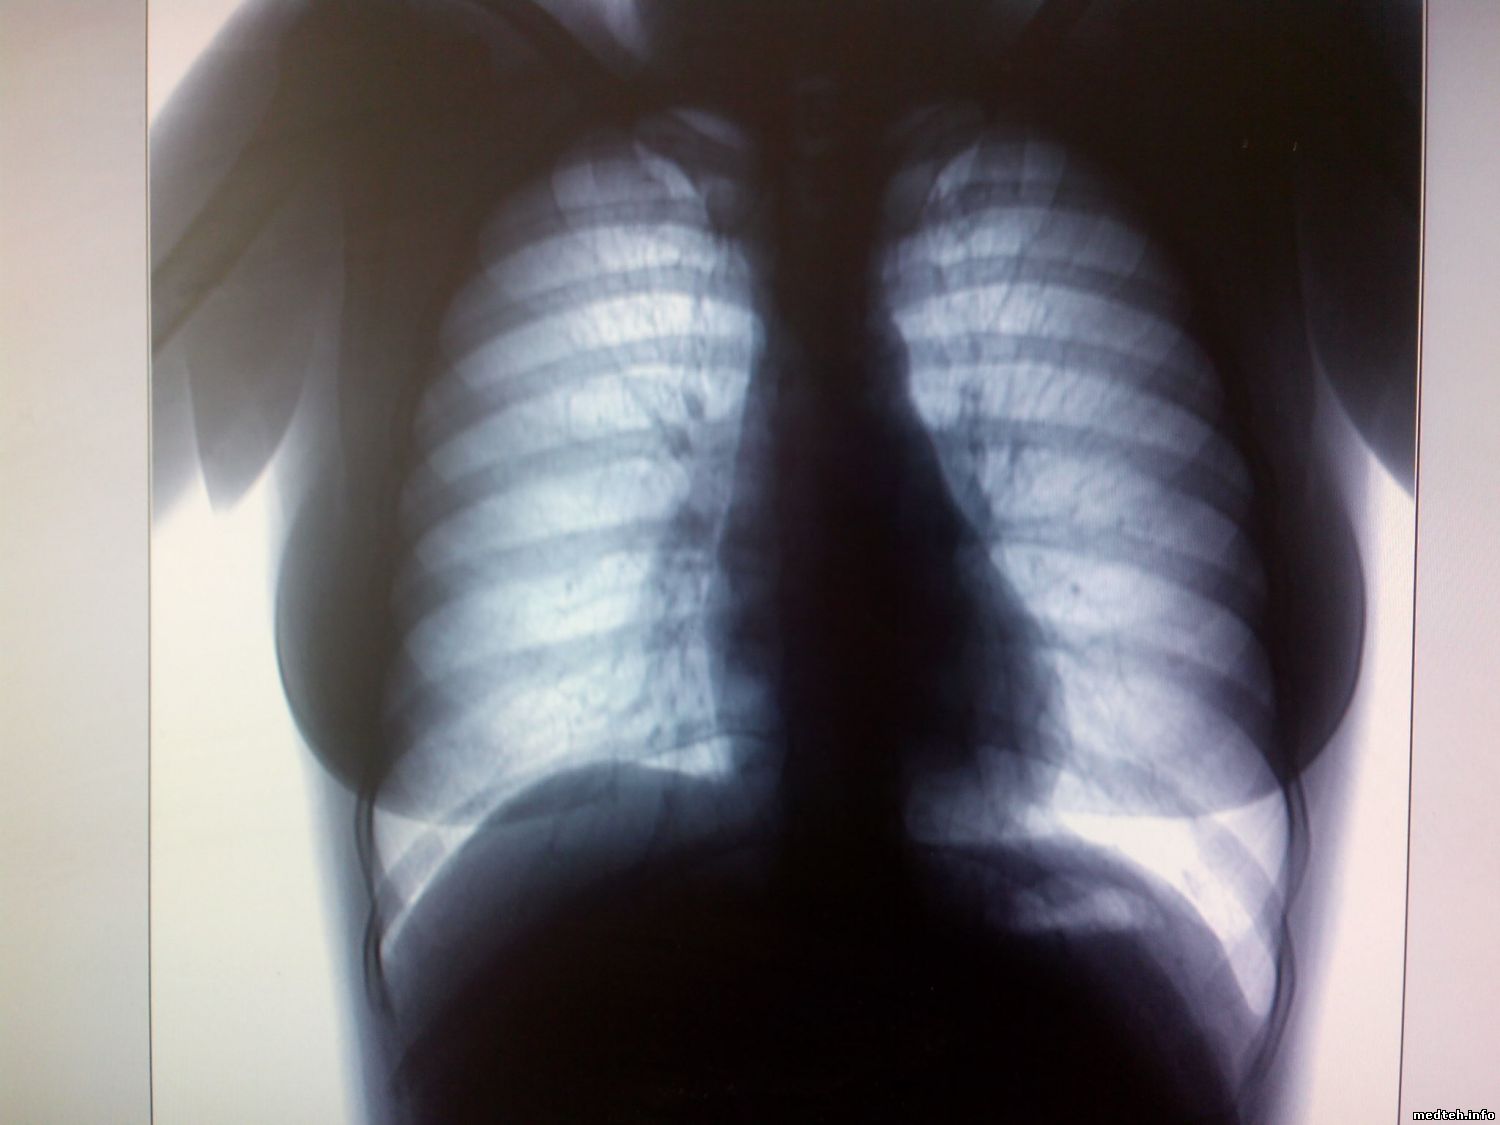

Добрый день. У меня есть на обслуге флюорограф ФЦМБ- РЕНЕКС-ФЛЮОРО, телефонная трубка, генератор Sedecal. Аппарат работает штатно, никаких ошибок не возникает. Снимок проходит нормально, генератор нормально пикает во время снимка. А вот сам снимок на мониторе мутный не чёткий, не читабельный. Образцы снимков прилагаю. Я вскрыл аппарат, ни каких разрушений, обрывов нет, передёрнул все разъемы в камере и в компьютере. Результата нет. Образцы снимков прилагаю. Из трёх снимков один вполне нормальный

Добрый день. Вышел из отпуска и провел все выше упомянутые действия. Все питающие напряжения есть. Трубка не причем. Заземление компа и корпуса штатива произведено отдельными проводами и в одну точку. фокусировка в норме. Прилагаю последний снимок фантома от РУМ-20 с медным фильтром. Снизу видна чёрная полоса Микросхемы в кроватках ещё не менял.